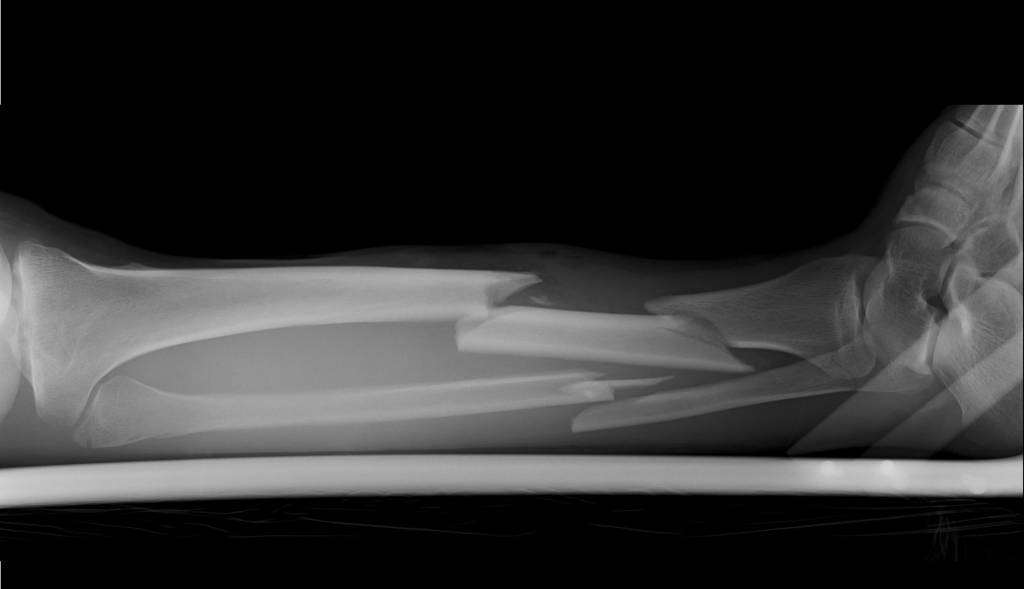

Unterschenkelbrüche entstehen allgemein meist durch Einwirkungen von Gewalt wie beispielsweise bei Verkehrsunfällen oder beim Sport. Schienbeinbrüche können verschiedene Formen annehmen, es kann sich um einen Schienbeinkopfbruch (Tibiakopffraktur), einen Schaftbruch (Tibiaschaftfraktur) oder einen Innenknöchelbruch (distale Tibiafraktur) handeln. Oftmals ist das Wadenbein ebenfalls gebrochen (Fibulafraktur).

Der Schienbeinbruch kann prinzipiell an drei verschiedenen Bereichen des Knochens auftreten. Grob lassen sich unterscheiden:

Als bildgebende Untersuchung genügt meist ein Röntgen, auch um den genauen Bruchverlauf zu sehen. Verletzungen der Umgebung des Knochens müssen aber ebenfalls beurteilt werden. So muss gegebenenfalls bei möglichen Gefäßschäden ein spezielles Ultraschall (Doppler-Sonografie) oder eine Röntgenuntersuchung mit Kontrastmittel (Angiographie) durchgeführt werden. Auch kommt bisweilen eine Computertomografie (CT) oder ein MRT (Magnetresonanz- oder Kernspintomographie) zum Einsatz.

Der Arzt teilt die Schienbeinbrüche nach der genauen Art sowie nach Schweregraden ein. Es gibt je nach der Stelle des Bruches unterschiedliche Klassifikationssysteme. Daraufhin kann die Behandlung geplant werden.